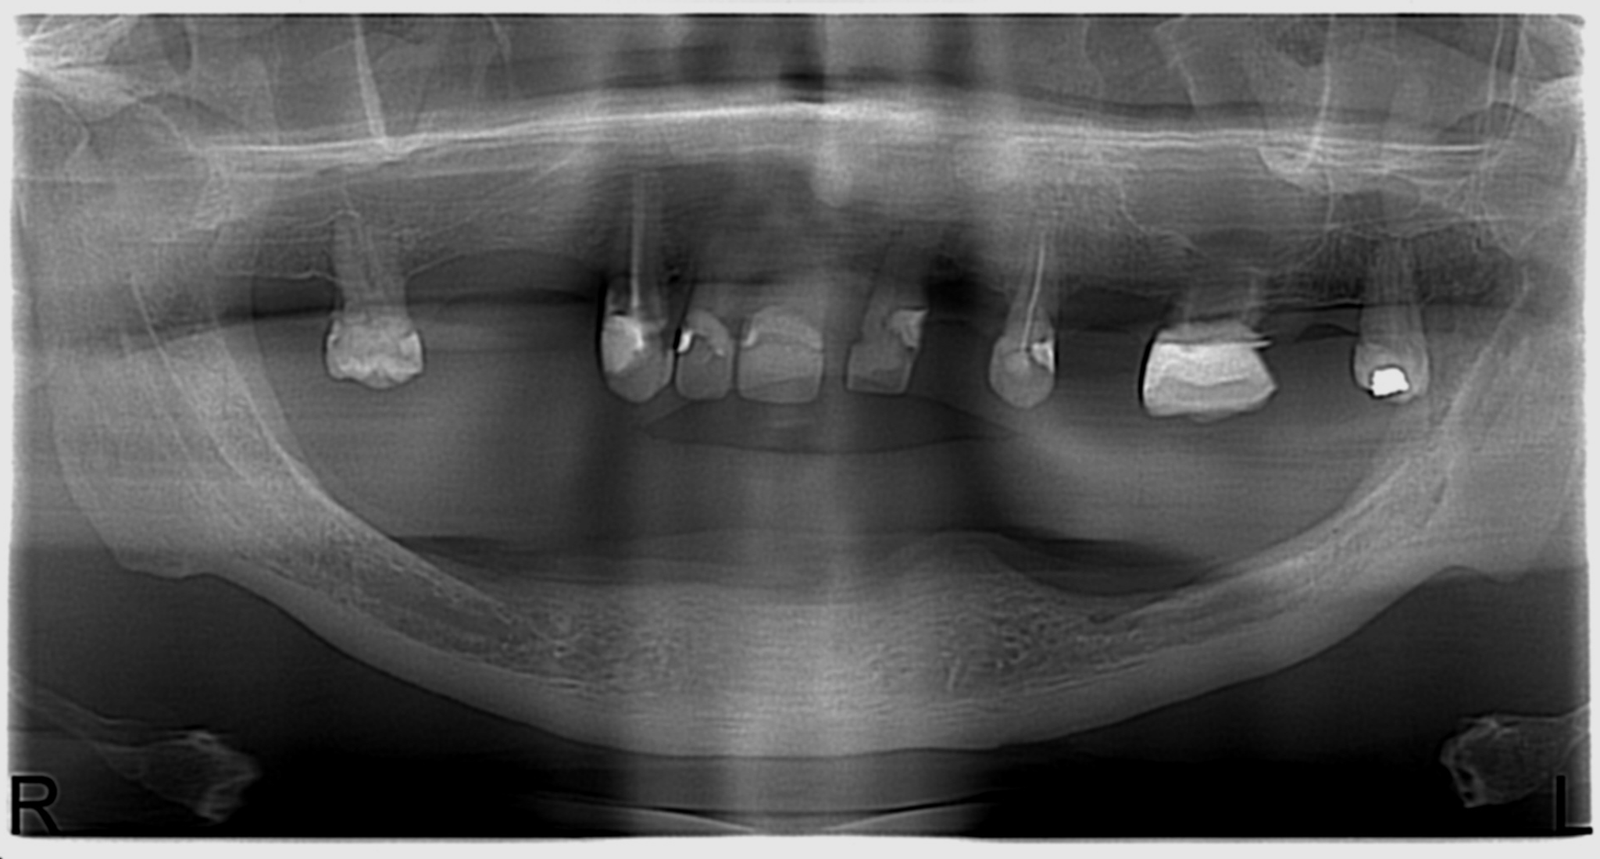

Réhabilitation complète avec mise en charge immédiate (4 implants bas / 6 implants haut)

Le patient se présente avec des dents qui bougent, en haut et en bas.

Nous avons commencé par la mâchoire inférieure avec 4 implants et une mise en charge immédiate.

Trois mois après, le haut a été fait avec le même principe avec 6 implants.

Cette fois-ci, il existait un déficit osseux, résolu par une technique d’expansion sans avoir recours à la greffe d’os.

Les prothèses réalisées sont vissées, ce qui permet de les enlever, les nettoyer une fois par an, ou résoudre n’importe quel problème.